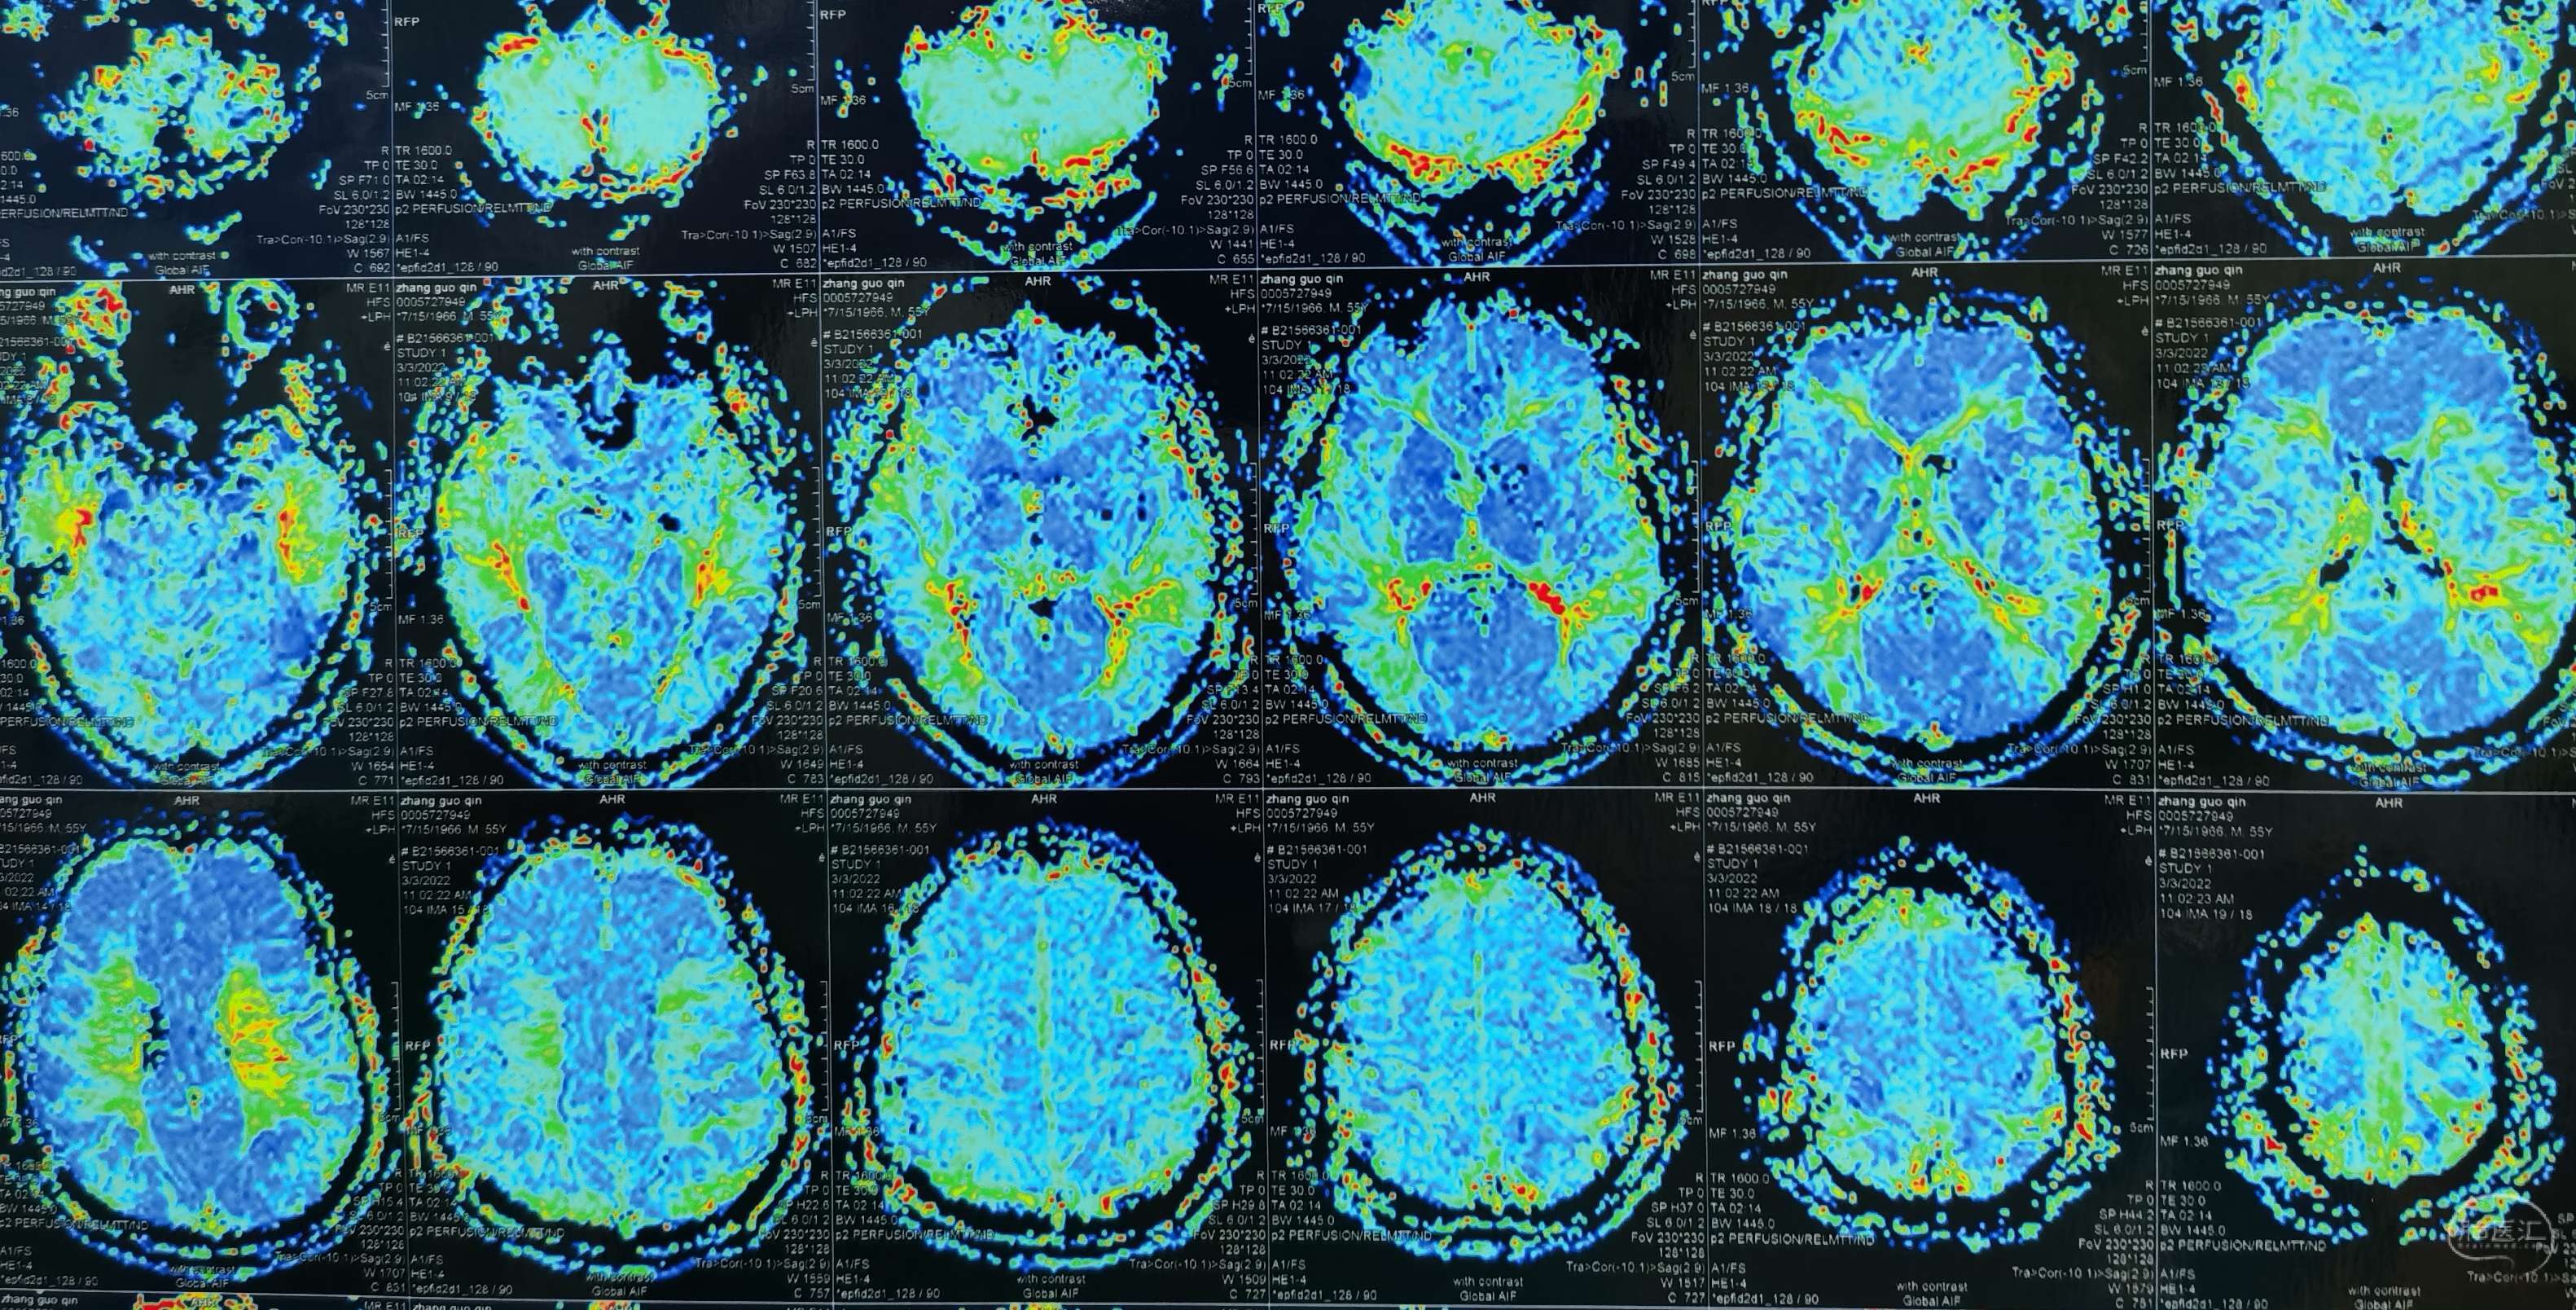

脑灌注提示:左侧大脑半球低灌注缺血。

脑灌注提示:右侧大脑半球低灌注缺血。

脑灌注提示:双侧大脑半球低灌注缺血。

脑灌注提示:双侧大脑半球低灌注缺血。

脑灌注提示:双侧大脑半球低灌注缺血。